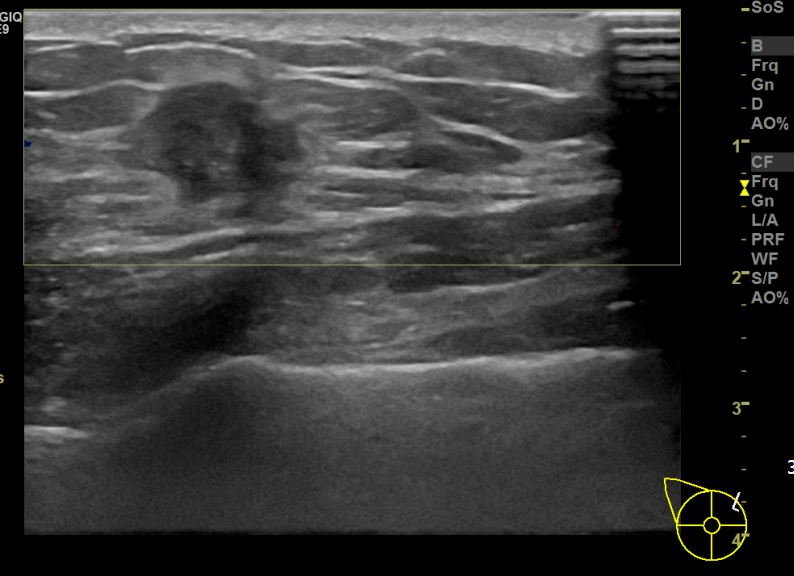

아산유외과개원후 670번째 유방암진단

상기환자 외부검사상 이상소견으로 내원하신 40대여성으로 우측에 의심스러운혹 조직검사시행해 유방암 진단되었습니다.